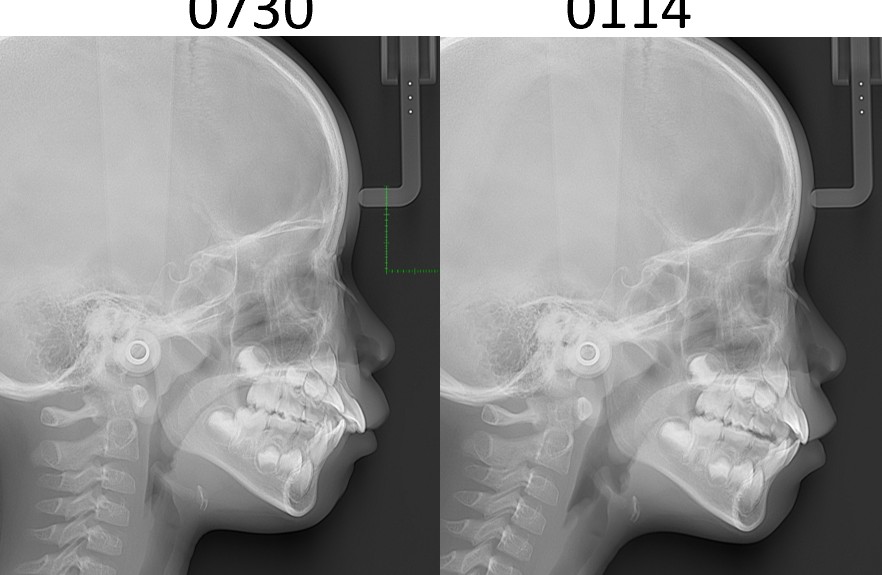

①①レントゲン写真:頭部X線規格写真(セファログラム)など検査をしている

患者さんの顎顔面の成長バランスや成長方向、量の予測をするために不可欠な検査です。